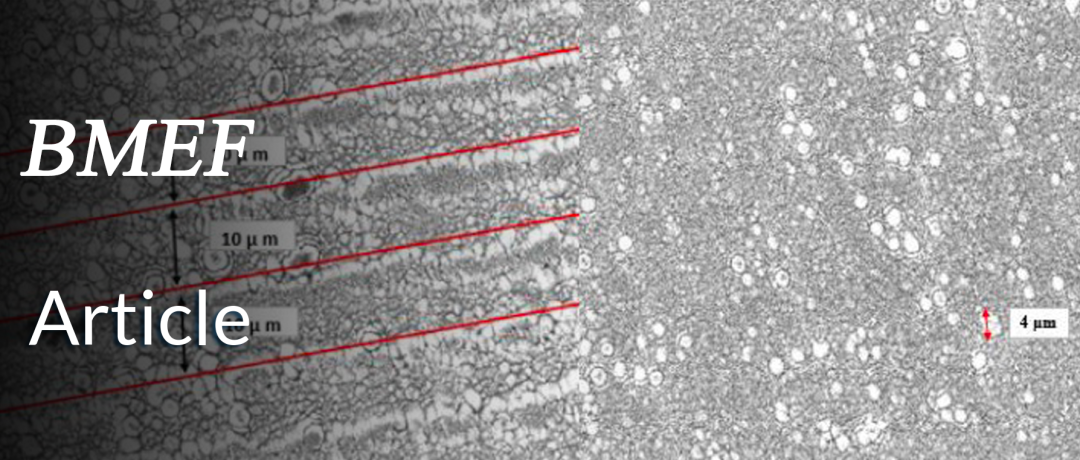

首先,作者团队利用选定的激光功率、速度和间距参数构建所需的激光诱导周期性表面微结构(Laser-Induced Periodic Surface Structures,LIPSS)。作者利用扫描电子显微镜(Scanning Electron Microscopy,SEM)扫描激光加工钛表面,可以观察到10 µm的间距,然后是散布在具有4 µm大小颗粒的多孔表面上的氧化钛(图1)。

随后,作者团队利用小鼠胚胎成纤维细胞(Mouse Embryonic Fibroblast Cells ,MEF)在钛样品上生长以评估细胞与具有不同拓扑结构的表面之间的相互作用。在与MEF细胞一起培养后,将样品固定并再次通过SEM进行观察,其中作为对照组的十字区域显示了使用抛光钛的结果(图2),对照组显示出更高的细胞密度和细胞增殖(图2),但在更高放大倍率下对细胞的观察显示出相似的细胞形态(图3)。由于细胞呈细长形状是成纤维细胞的特征,因此可以认为该表面适合MEF细胞粘附,并且不会引起细胞毒性作用。

图 2:对照组的扫描电子显微镜结果(放大100倍)